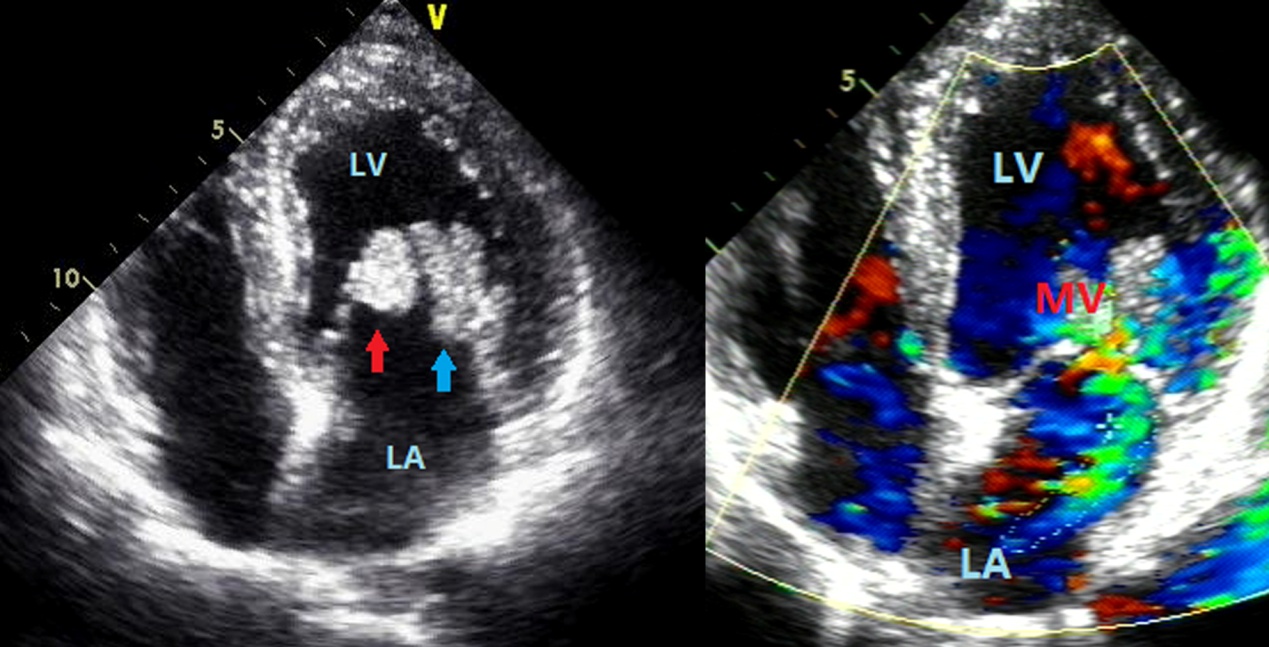

A 58-year-old male was referred to our institution for further evaluations in a context of sudden syncope from unknown cause two months before. He had a 40-year history of cigarette-smoking and alcohol consumption. His initial vital signs were documented as normal range. No jugular venous distention or lower extremity edema was noted. Grade 3/6 systolic murmurs at the cardiac apex were heard on auscultation. The syncope work-up including head MSCT, carotid Doppler, electroencephalogram, electrocardiogram, and orthostatic blood pressure were all negative. Transthoracic echocardiography showed several uniform hyper echogenic masses adhered to the anterior and posterior leaflets of the mitral valve (Figure 1a), which rendered obvious mobility and some deformability following the cardiac cycle. The neoplasms measured 20 × 13 mm and 21 × 12 mm respectively. Colour Doppler flow imaging (CDFI) displayed slight-to-moderate regurgitation signal at the mitral orifice (Figure 1b). Cardiac MSCT angiography showed a lobulated filling defect in the left atrium and ventricle, closely contacting with the mitral valve annulus and mitral leaf lets (Figure 2a and 2b). Neoplasm was more likely to originate from the mitral valvular region and crossed the left cardiac chamber. Given the highly mobile nature of this mass and the incidence of embolic phenomena, cardiac MRI with contrast administration was conducted as a prelude to surgical intervention. The MRI scan showed the presence of multiple masses attached to the anterior and posterior mitral valve leaflets. On cine black blood steady-state free precession imaging, the mass was noted to be of high intensity (Figure 3a). The neoplasms remained in the left atrium during systole, and prolapsed freely into the left ventricle during diastole (Figure 3b and 3c). On early Gadolinium-enhanced images, the mass was hypointense. Mild patchy enhancement was observed on late Gadolinium (Figure 3d). According to imaging findings above, multiple myxomas of the mitral valve were preoperatively proposed.

Figure 1: The diastolic period of apical four-chamber view indicated two tumors adherent to the anterior and posterior mitral valves. CDFI revealed a slight-to-moderate regurgitation signal at the mitral valve during the systolic period.